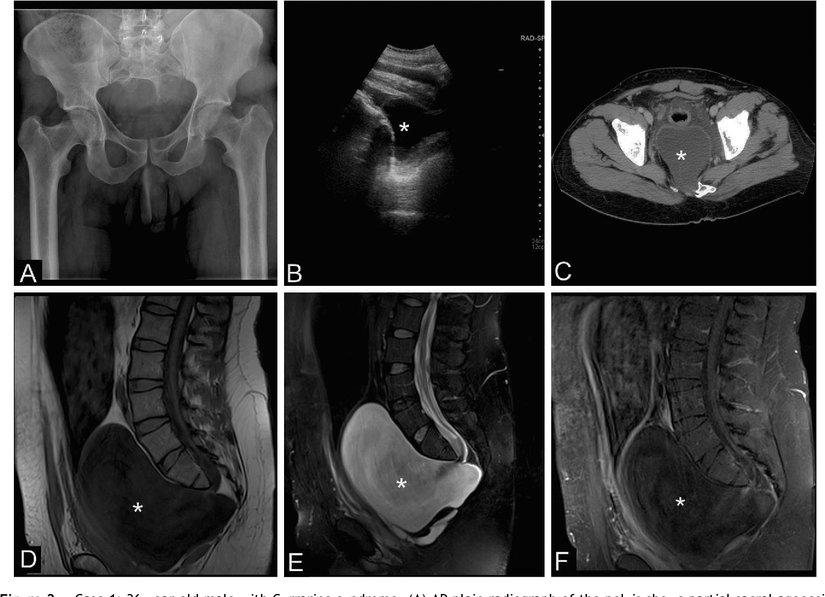

Radyolojik Tanı Yöntemleri

Kaudal Regresyon Sendromu'nun tanısı için farklı yöntemler kullanılabilir. Bunlardan biri fetal ultrasonografidir. Ultrason, gelişmekte olan fetüsün bir görüntüsünü oluşturmak için yüksek frekanslı ses dalgalarını kullanan bir görüntüleme yöntemidir. Bu yöntemle, sendromla ilişkili bazı kusurları tespit edilebilir. Sonrasında bulguları değerlendirmek için ekokardiyografi gibi ek tetkikler gerekebilir.

Spinal defektler gibi belirli anomalilerin derecesini değerlendirirken manyetik rezonans görüntüleme (MR) de yapılabilir. Bu yöntem, belirli organların ve vücut dokularının kesit görüntülerini üretmek için manyetik bir alan ve radyo dalgaları kullanır.